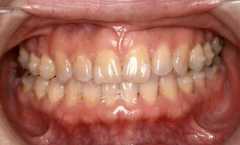

上下の歯の裏側にブラケット装置をつけている治療例

*新宿の常盤矯正歯科医院より写真提供

見た目には歯列矯正をしているようには見えませんが、歯の裏側に矯正装置のブラケットが付いています。